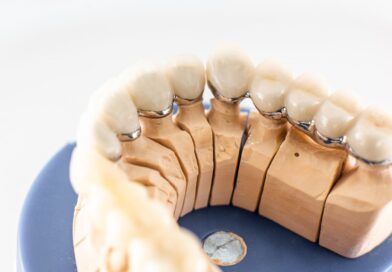

Ağız ve Diş Sağlığı